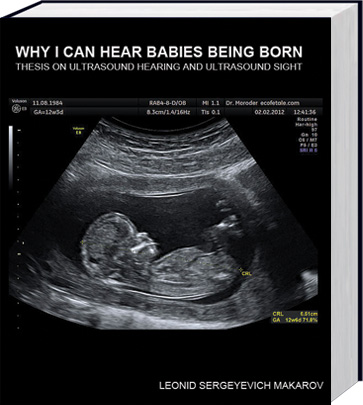

Why I can hear babies being born: thesis on ultrasound hearing and ultrasound sight is available for purchase at your local store.

ISBN: 9789612821050

No. pages: 450 + included DVD

Price: $59, 59 EUR, 59 British pounds